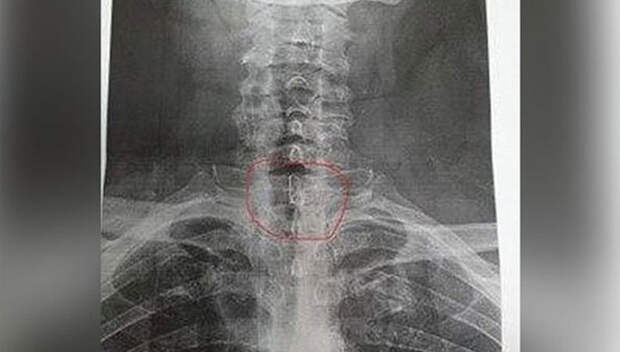

Медики столичной больницы звлекли из пищевода 68-летнего москвича рыболовный крючок. Пенсионер поступил в клинику с рыболовной леской, которая торчала у него изо рта, и жаловался на то, что ему трудно глотать. Оказалось, он случайно проглотил крючок вместе с редиской.